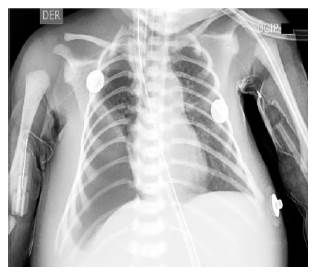

Luego de 18 horas de postoperatorio, se observa disminución rápida de la saturación de oxígeno, por lo cual se aumenta el soporte ventilatorio y se toma una radiografía de tórax (Ver figura 4) que muestra radiopacidad en los 2/3 inferiores del hemitórax derecho, que al examen ecográfico es concordante con hemotórax a este nivel y se procede a la realización de toracostomía cerrada y drenaje pleural continuo con Pleurovac®, el cual fue retirado luego de 30 días. El paciente continuó en cuidado intensivo con mejoría de los parámetros gasométricos y con soporte hemodinámico y ventilatorio. Se da egreso de unidad de cuidado intensivo neonatal a los 57 días con soporte de oxígeno por cánula nasal, tolerancia a la nutrición enteral y manejo broncodilatador. Luego de 72 días de estancia hospitalaria se da egreso, con vigilancia ambulatoria por diferentes especialidades y manejo farmacológico con broncodilatador.

Fuente: autores.

Figura 4 Radiografía de tórax con presencia de hemotórax derecho.